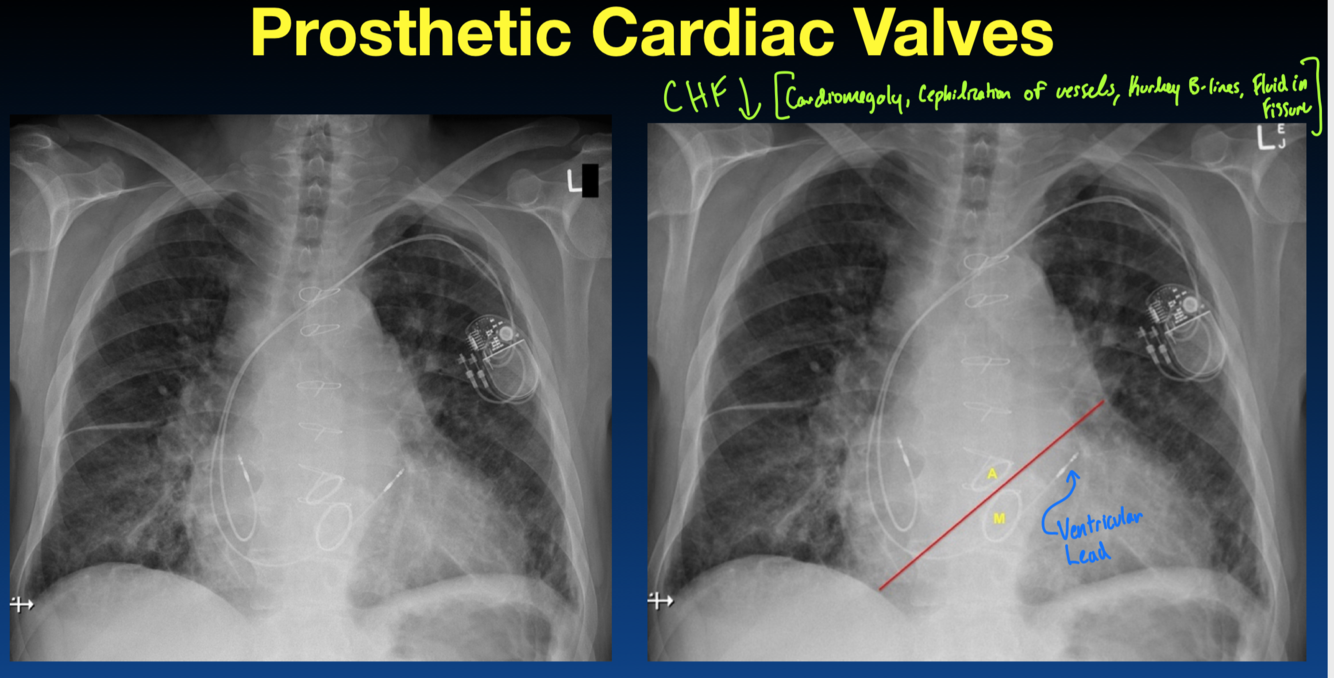

Where are the aortic and mitral valves here?

What is shown here?